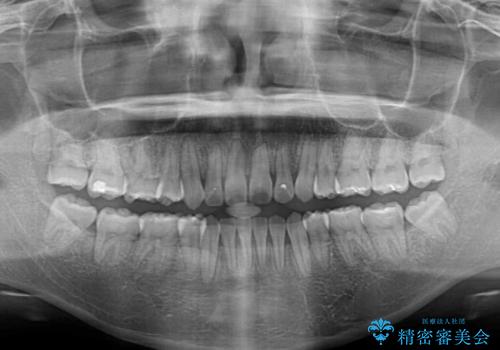

非常にスムーズに歯列移動が行われ、当初は2-2.5年を予想していましたが、僅か1年4ヶ月で治療を終えることができました。